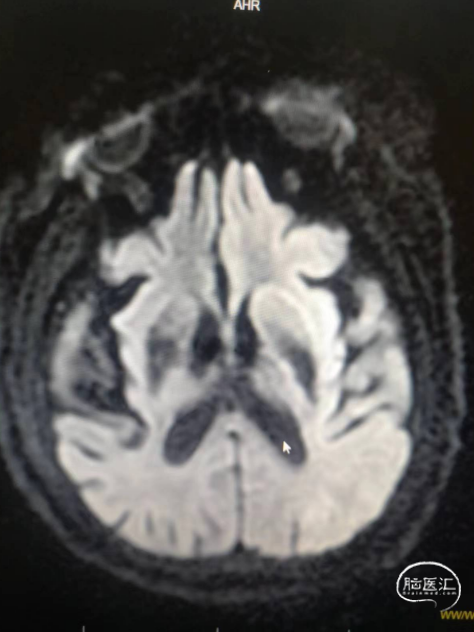

术前影像信息

符合脑内多发缺血变性灶、梗死灶(左侧大脑半球大面积急性梗死)、软化灶T2-FLAIR/DWI表现;

符合颅脑动脉硬化并多发狭窄MRA表现,左侧颈内动脉颅内段、大脑中动脉及分支未见显示,考虑闭塞或重度狭窄,建议CTA进一步检查。